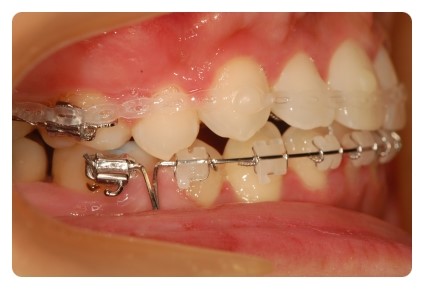

치아에 고무줄이 많이 걸려있으니 양치질이 깨끗하게 잘 안되요 ㅠㅠ

아래 잇몸이 부어서 밀려올라왔네요